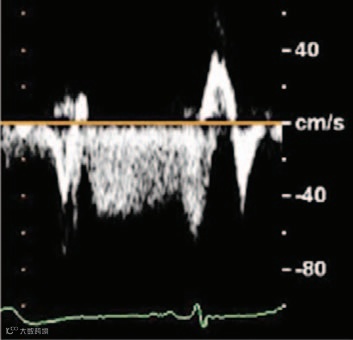

显示肿瘤内部有动态烟雾样回声(提示存在自发显影,图3;视频I)。M型超声显示肿瘤在收缩期两次回弹至左心房腔,产生M形信号(图4;视频II),提示肿瘤内部充满液体而非凝血,呈现血球样外观。彩色多普勒显示有血流流入(图5)和流出肿瘤(图6),且主要发生在舒张期(图7和8;视频III),提示血供来源于冠状动脉。

本病例中,肿瘤内部结构的特征对于准确诊断至关重要。自发显影提示肿瘤内部独特的液态而非凝血环境。此外,肿瘤产生M形信号的细微运动值得关注,这可能是由于内部液体成分比重不均所致。